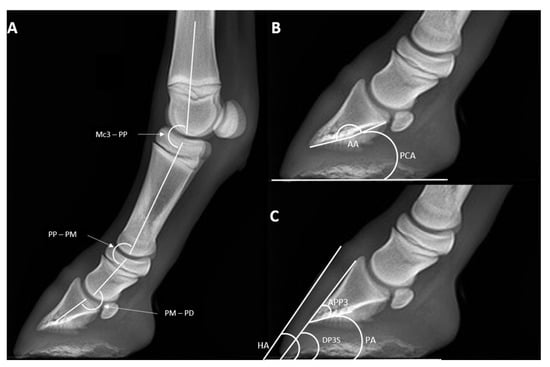

| HA | DPDS | PA | PCA | AA | APPD | Mc3-PP | PP-PM | PM-PD | |

|---|---|---|---|---|---|---|---|---|---|

| T0 | 66.9 ± 5.4 | 62.1 ± 3.2 | 10.3 ± 6.5 | 33.6 ± 2.1 | 169.9 ± 2.5 | 38.3 ± 2.9 | 164.1 ± 2.4 | 169.9 ± 2.3 | 178.4 ± 10.7 |

| p-value | 0.54 | 0.35 | 0.25 | 0.71 | 0.99 | 0.80 | 0.72 | 0.63 | 0.97 |

| T1 | 64.6 ± 4.1 | 57.9 ± 5.6 | 4.9 ± 4.3 | 28.0 ± 9.6 | 169.1 ± 6.9 | 36.7 ± 2.4 | 156.3 ± 8.0 | 166.8 ± 4.1 | 179.7 ± 4.1 |

| p-value | 0.33 | 0.31 | 0.17 | 0.11 | 0.25 | 0.29 | 0.62 | 0.11 | 0.67 |

| T2 | 61.9 ± 5.1 | 55.5 ± 2.9 | 6.9 ± 2.0 | 24.2 ± 4.8 | 169.1 ± 5.2 | 36.3 (36.0–39.5) | 156.6 (147.9–165.3) | 165.8 ± 5.2 | 181.9 ± 5.6 |

| p-value | 0.45 | 0.74 | 0.13 | 0.63 | 0.41 | 0.01 | 0.03 | 0.36 | 0.75 |

| T3 | 60.2 ± 1.6 | 53.7 ± 2.1 | 5.5 ± 3.7 | 23.5 ± 6.2 | 171.4 ± 6.4 | 35.9 ± 1.7 | 155.0 ± 3.4 | 163.1 ± 1.9 | 177.7 ± 7.3 |

| p-value | 0.83 | 0.40 | 0.07 | 0.56 | 0.35 | 0.11 | 0.71 | 0.30 | 0.73 |

| T4 | 64.3 ± 1.8 | 52.9 ± 3.7 | 4.7 ± 0.8 | 24.6 ± 6.3 | 169.1 ± 4.0 | 36.8 ± 1.4 | 153.9 ± 1.3 | 162.6 ± 2.9 | 181.5 ± 3.3 |

| p-value | 0.63 | 0.76 | 0.94 | 0.50 | 0.20 | 0.70 | 0.96 | 0.87 | 0.58 |

| T5 | 57.6 ± 2.9 | 53.3 ± 3.6 | 3.2 ± 2.2 | 23.9 ± 5.8 | 171.5 ± 5.1 | 37.8 ± 1.7 | 158.2 ± 2.6 | 161.9 ± 2.0 | 177.9 ± 7.8 |

| p-value | 0.10 | 0.91 | 0.29 | 0.24 | 0.99 | 0.22 | 0.23 | 0.80 | 0.58 |

| T6 | 54.6 ± 3.8 | 51.2 (50.5–58.3) | 3.0 (2.8–6.0) | 25.7 ± 10.9 | 170.8 ± 4.7 | 36.6 ± 1.8 | 163.8 ± 2.3 | 164.7 ± 4.8 | 181.4 ± 13.8 |

| p-value | 0.43 | 0.02 | 0.01 | 0.29 | 0.86 | 0.07 | 0.90 | 0.09 | 0.12 |